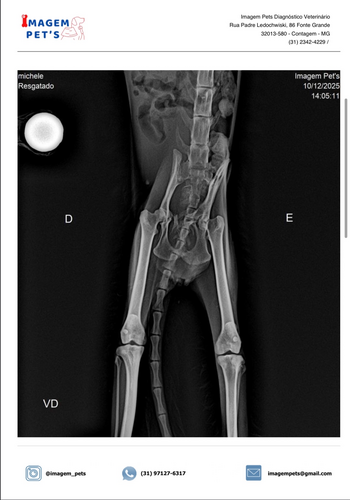

Olá pessoal! Hoje venho pedir a ajuda de vocês para mudar o destino da minha gatinha recém resgatada. Ela foi encontrada em situação muito delicada: extremamente desidratada, com múltiplas fraturas e sem forças para continuar lutando sozinha.

Mesmo diante de tanta dor, ela ainda encontra coragem para miar baixinho e pedir carinho. Nós não podíamos virar as costas! Ela já está recebendo atendimento, mas os custos com exames, internação, medicamentos e cirurgia são além do que posso pagar, e precisamos unir forças para garantir o tratamento completo e uma recuperação digna.